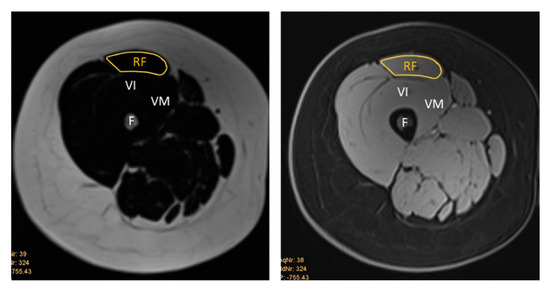

Background/Objectives: Sarcopenia, an underdiagnosed musculoskeletal disorder, is a serious cause of disability, poor quality of life, and healthcare costs in an increasingly elderly population. This study aimed to examine an ultrasound (US)-based, inexpensive, simple, and reproducible alternative to magnetic resonance imaging (MRI) for assessing muscle quality. A study compared Dixon MR fat fraction with US attenuation imaging (ATI) and echo intensity (EI) in the rectus femoris (RF) and biceps brachii (BB). Methods: The US images were acquired from 34 participants who had previously received a whole-body MRI. The ATI measurements were carried out using a linear array on a Canon Aplio i800 scanner. The measurements of EI were assessed by manually tracing the cross-sectional border of the right RF and BB muscles. Corresponding T1-weighted Dixon VIBE-based fat and water images were required for the MRI fat fraction percentage (MR %FF) measurements. Results: Using Pearsons correlation coefficient, a good correlation was found between MR %FF and EI measurements. The results between operators’ measurements showed a strong correlation and were highly repeatable. Attenuation imaging revealed no correlation with MR %FF or EI. Conclusions: Echo intensity offers a low-cost, non-invasive, and widely accessible US-based imaging modality for screening patients at risk for sarcopenia. No correlation was found between the ATI and MR %FF or between the ATI and EI. Further adapted protocols and software adjustments are needed so that ATI has the potential to prove itself as an additional US-based method for assessing fat infiltration in muscles. Full article

Show Figures

Figure 1